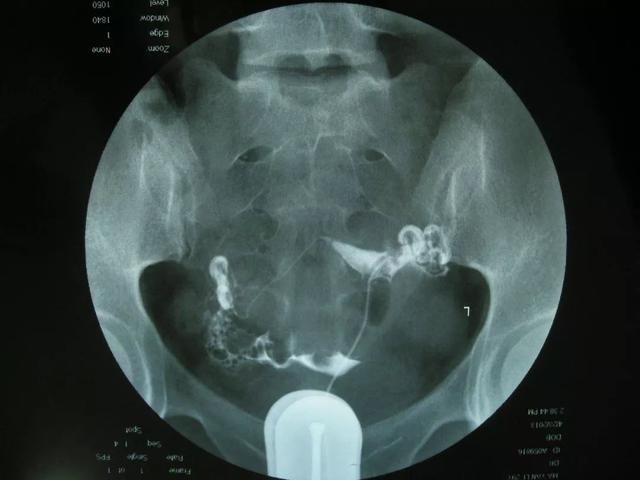

输卵管造影是通过给女性的子宫输卵管做X线检查,查看输卵管的通畅程度来判断是否是由于输卵管堵塞导致不孕。通过这样的方式进行检查,对于人体的损害是非常小的,而且准确度接近百分之百,比起B超、CT及做输卵管镜来说,对人身损伤更小,而且检查的准确度更高。

优势二:通过子宫输卵管造影检查,可以准确检查输卵管是否通畅、不孕是原发性的还是继发性的、子宫为什么会异常出血及各种子宫内的问题。通过造影检查后可以准确判断出来具体是哪一种症状。

输卵管造影除了可以检查和治疗因为输卵管堵塞导致的不孕症之外,对于子宫异常出血、输卵管再通、子宫肌瘤及子宫畸形、宫颈粘连等都可以检查出来。